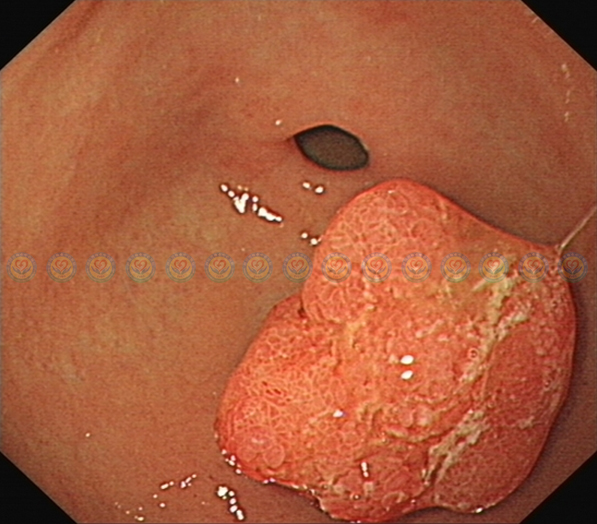

肿块退回胃内,其直径在3cm以上,且存在粗蒂,考虑内有粗大滋养血管。直接电切有较高出血风险。